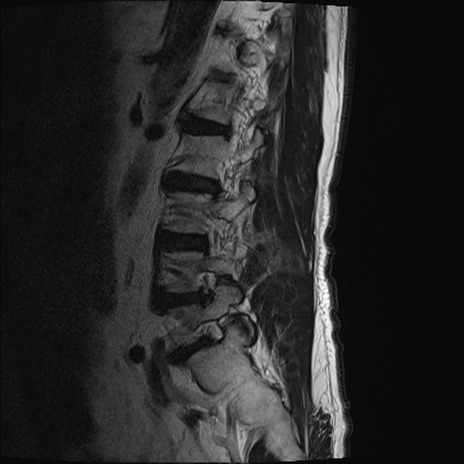

【整形】TIPS症例2 腰椎MRI T2WI(矢状断像)

【症例】70歳代男性

【主訴】左下肢痛

【現病歴】2週間前くらいから腰痛、左下肢痛あり。左臀部から大腿、下腿外側のしびれが常時ある。歩行とともに同部位の痛みあり。

【身体所見】Lasegue70-/60+、Bragard-/±、PTR ±/±、ATR -/-、IP 5/5、TA 5/4、TS 5/5、EHL 右第1足趾なし/3、FHL 5/5、hypersthesia(-)、足背動脈触知良好

異常所見と診断は?